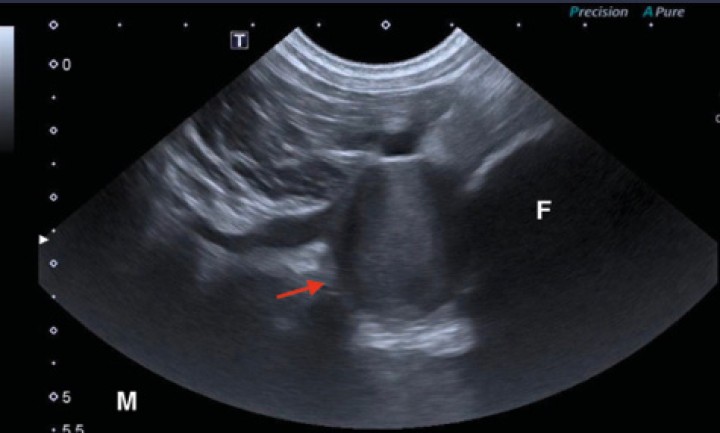

Se exploró ecográficamente la zona diafisaria del fémur derecho (Toshiba Xario 200, Canon Medical, Madrid) utilizando una sonda microconvexa con rango de frecuencias de 6 a 11 MHz. Se visualizó la lesión ósea descrita en otras pruebas. La cortical era irregular y discontinua, con un halo hipoecoico en el tejido blando. Junto a ella se halló una estructura hipoecoica redondeada y de pared fina (Fig. 4, video 1). La señal Doppler color de esta lesión era positiva con apariencia de remolino con color alternante rojo y azul (“signo de ying-yang”) (Fig. 5, video 2).

<p>Imagen ecográfica en plano transversal desde el aspecto caudal del fémur. La izquierda de la imagen corresponde a la zona lateral de la extremidad. A nivel lateral se visualiza una estructura hiperecoica de superficie irregular con sombra acústica compatible con la cortical femoral alterada ya descrita. En íntimo contacto con ella se observa una estructura redondeada, de contenido hipoecoico y con estrecha relación con la vascularización regional sugestiva de lesión aneurismática (flecha roja). “L”: lateral; “F”: fémur.</p>

Imagen ecográfica en plano transversal desde el aspecto caudal del fémur. La izquierda de la imagen corresponde a la zona lateral de la extremidad. A nivel lateral se visualiza una estructura hiperecoica de superficie irregular con sombra acústica compatible con la cortical femoral alterada ya descrita. En íntimo contacto con ella se observa una estructura redondeada, de contenido hipoecoico y con estrecha relación con la vascularización regional sugestiva de lesión aneurismática (flecha roja). “L”: lateral; “F”: fémur.

El paciente acudió a visita de control un mes después. Se revisó ecográficamente la lesión vascular de la zona femoral derecha. La estructura aneurismática no presentaba señal Doppler y su contenido no era anecoico, como en el estudio inicial, sino ecogénico (Fig. 7). Los vasos adyacentes a esta lesión eran econormales y con señal Doppler que indicaba permeabilidad. Estos cambios eran compatibles con trombosis en el presunto pseudoaneurisma.

<p>Imagen ecográfica en plano transversal de la región caudodistal del fémur derecho. A la derecha de la imagen se observa una estructura de superficie hiperecoica con sombra acústica que representa la cortical femoral. Se observa una lesión redondeada con contenido ecogénico (flecha roja) que contrasta con el contenido hipoecoico de la vena femoral adyacente. Este hallazgo es compatible con trombosis de la estructura aneurismática visualizada en estudios anteriores. Estudio realizado 1 mes después de la primera ecografía. “M”: medial; “F”: fémur.</p>

Imagen ecográfica en plano transversal de la región caudodistal del fémur derecho. A la derecha de la imagen se observa una estructura de superficie hiperecoica con sombra acústica que representa la cortical femoral. Se observa una lesión redondeada con contenido ecogénico (flecha roja) que contrasta con el contenido hipoecoico de la vena femoral adyacente. Este hallazgo es compatible con trombosis de la estructura aneurismática visualizada en estudios anteriores. Estudio realizado 1 mes después de la primera ecografía. “M”: medial; “F”: fémur.